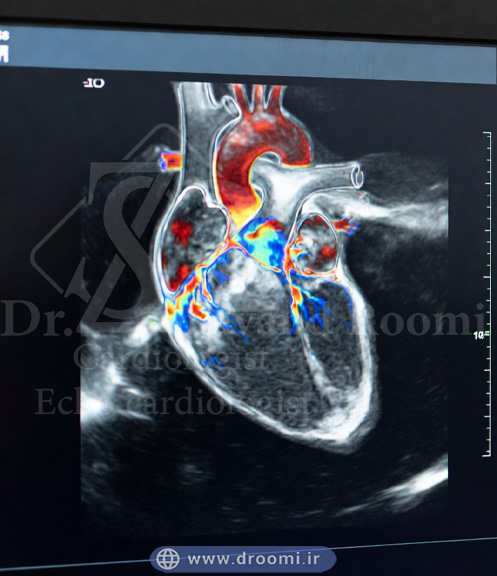

اکو داپلر رنگی قلب (که به آن اکوکاردیوگرافی داپلر رنگی یا اکو قلب رنگی نیز گفته میشود) یک روش پیشرفته تصویربرداری غیرتهاجمی از قلب است که نه تنها ساختار قلب را نشان میدهد، بلکه جریان خون داخل حفرهها، دریچهها و عروق بزرگ را به صورت رنگی و واقعی نمایش میدهد. این فناوری بر پایه امواج صوتی اولتراسوند کار میکند و با استفاده از اثر داپلر، جهت، سرعت و الگوی جریان خون را به طور دقیق ارزیابی میکند.

در تصاویر اکو داپلر رنگی، جریان خون به سمت پروب (دستگاه) معمولاً با رنگ قرمز و جریان دور شونده با رنگ آبی نشان داده میشود. اگر جریان خون آشفته (توربولنت) باشد، رنگ سبز یا زرد اضافه میشود تا ناهنجاریها مانند نشت دریچه یا تنگی عروق برجسته شوند.

تصویر آموزشی که پیشرفت اکو داپلر رنگی قلب را با ترکیب تصویر دوبعدی و جریان خون رنگی نمایش میدهد.

این تصویر تفاوت اصلی اکو داپلر رنگی و اکو قلب معمولی را با نمایش لایه رنگی جریان خون نشان میدهد.

تکنیک داپلر رنگی یک لایه پیشرفته به اکوکاردیوگرافی پایه اضافه میکند و نه تنها ساختار قلب را نشان میدهد، بلکه جریان خون را به صورت رنگی و واقعی نمایش میدهد. این فناوری بر پایه اصل فیزیکی اثر داپلر کار میکند و تفاوت اصلی اکو رنگی با اکو معمولی را تشکیل میدهد.

تبدیل دادههای سرعت به رنگ (قرمز برای جریان به سمت پروب، آبی برای دور شدن)

در اکوکاردیوگرافی داپلر رنگی، دادههای سرعت و جهت به رنگ تبدیل میشوند و روی تصاویر دوبعدی سیاهوسفید superimpose (همپوشانی) میگردند. به طور استاندارد:

– جریان خون به سمت پروب (نزدیک شدن) با رنگ قرمز نشان داده میشود.

– جریان خون دور شونده از پروب با رنگ آبی نمایش داده میشود.

شدت رنگ (روشنتر یا تیرهتر) نشاندهنده سرعت بالاتر یا پایینتر است. این کد رنگی (معروف به BART: Blue Away, Red Toward) به پزشکان کمک میکند تا جهت طبیعی یا غیرطبیعی جریان را سریع تشخیص دهند.

عملکرد زنده دریچههای قلب در اکو داپلر رنگی که جریان خون را با رنگهای زنده و پویا نمایش میدهد

تصاویر اکو داپلر رنگی یکی از قدرتمندترین ابزارهای بصری در کاردیولوژی هستند، زیرا نه تنها ساختار قلب را نمایش میدهند، بلکه عملکرد واقعی جریان خون را به صورت زنده و رنگی نشان میدهند. این تصاویر به پزشک اجازه میدهند تا در لحظه مشکلات پنهان را تشخیص دهد و تصمیمگیری دقیقتری داشته باشد.

نمونه تصاویر واقعی (قلب طبیعی vs غیرطبیعی) با توضیح رنگها

یک قلب طبیعی، دارای جریان خون منظم و آرام (لامینار) است و رنگها یکنواخت و جهتدار هستند:

<strong>- در فاز پر شدن بطنها (دیاستول)، خون از دهلیزها به بطنها جریان مییابد و معمولاً به سمت پروب (قرمز) نشان داده میشود.

<strong&gt;- فاز انقباض (سیستول)، خون از بطنها به سمت آئورت و شریان ریوی خارج میشود و اغلب آبی یکنواخت است.

در قلب غیرطبیعی، الگوهای رنگی تغییر میکنند:

<p>yle=”padding-right: 40px;”>– نشت دریچه (رگورژیتاسیون): جت رنگی معکوس و آشفته دیده میشود؛ مثلاً در نارسایی دریچه میترال، جت قرمز-زرد-سبز از بطن چپ به دهلیز چپ در سیستول برمیگردد.

– تنگی دریچه: افزایش سرعت جریان در محل تنگی باعث ایجاد رنگهای روشنتر و مخلوط (علیرغم مساحت کوچک) میشود.

– سوراخ بینحفرهای (شانت): جریان غیرطبیعی بین سمت چپ و راست قلب با رنگهای متضاد و موزاییکی نمایش داده میشود.

این تفاوتهای رنگی به پزشک کمک میکند تا بدون نیاز به بررسیهای تهاجمی، شدت مشکل را تخمین بزند.